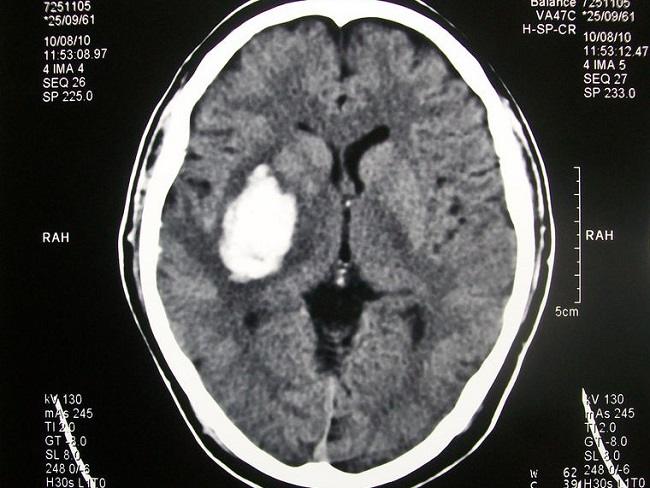

Target tekanan darah pada penatalaksanaan pendarahan intraserebral akut atau acute intracerebral hemorrhage (ICH) mungkin dapat mempengaruhi outcome ICH. Definisi ICH adalah kerusakan otak akut akibat rupturnya pembuluh darah otak yang menyebabkan ekstravasasi darah ke parenkim otak. Tujuan terapi adalah mencegah ekspansi pendarahan dan deteriorasi.[1]

Angka mortalitas akibat hal ini cukup tinggi, mencapai 30-40%. Insidens pendarahan intraserebral akut meningkat seiring bertambahnya usia. Faktor risiko utama yang lain adalah hipertensi dan penggunaan antikoagulan.[1]